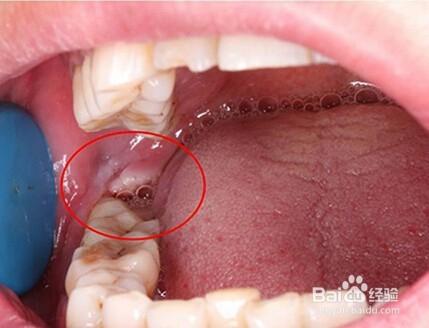

智齿萌发初期图片

长智齿前期的症状图片

长智齿初期图片

正常长智齿的症状图片

智齿长出来的前兆图片

智齿还没有长出来图片

智齿刚长一点出来图片